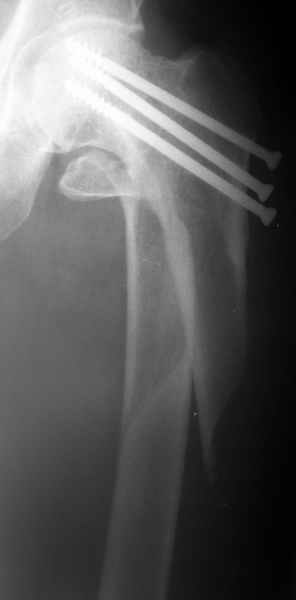

Bill Burman 16 Январь 2004, 08:08

See

another caseof a subtrochanteric fracture through screw holes for femoral neck fracture fixation.

That's a great case illustration provided by Bill and HWBF and the blade plate/valgus producing osteotomy looks like a good option for Alex's case.

A particularly interesting aspect of Alex's case is the 2 years since screw placement. We've been leaving proximal screws in place indefinitely for years and haven't seen very many late fractures around them. The problems, if they occur, tend to be loss of fixation or early fracture from distal or large or many drill holes or the occasional arthritic hip requiring screw removal for femoral prosthetic placement. Perhaps this fracture at two years post op is merely a very uncommon and unlucky patient? Or have others seen this specific problem more frequently?